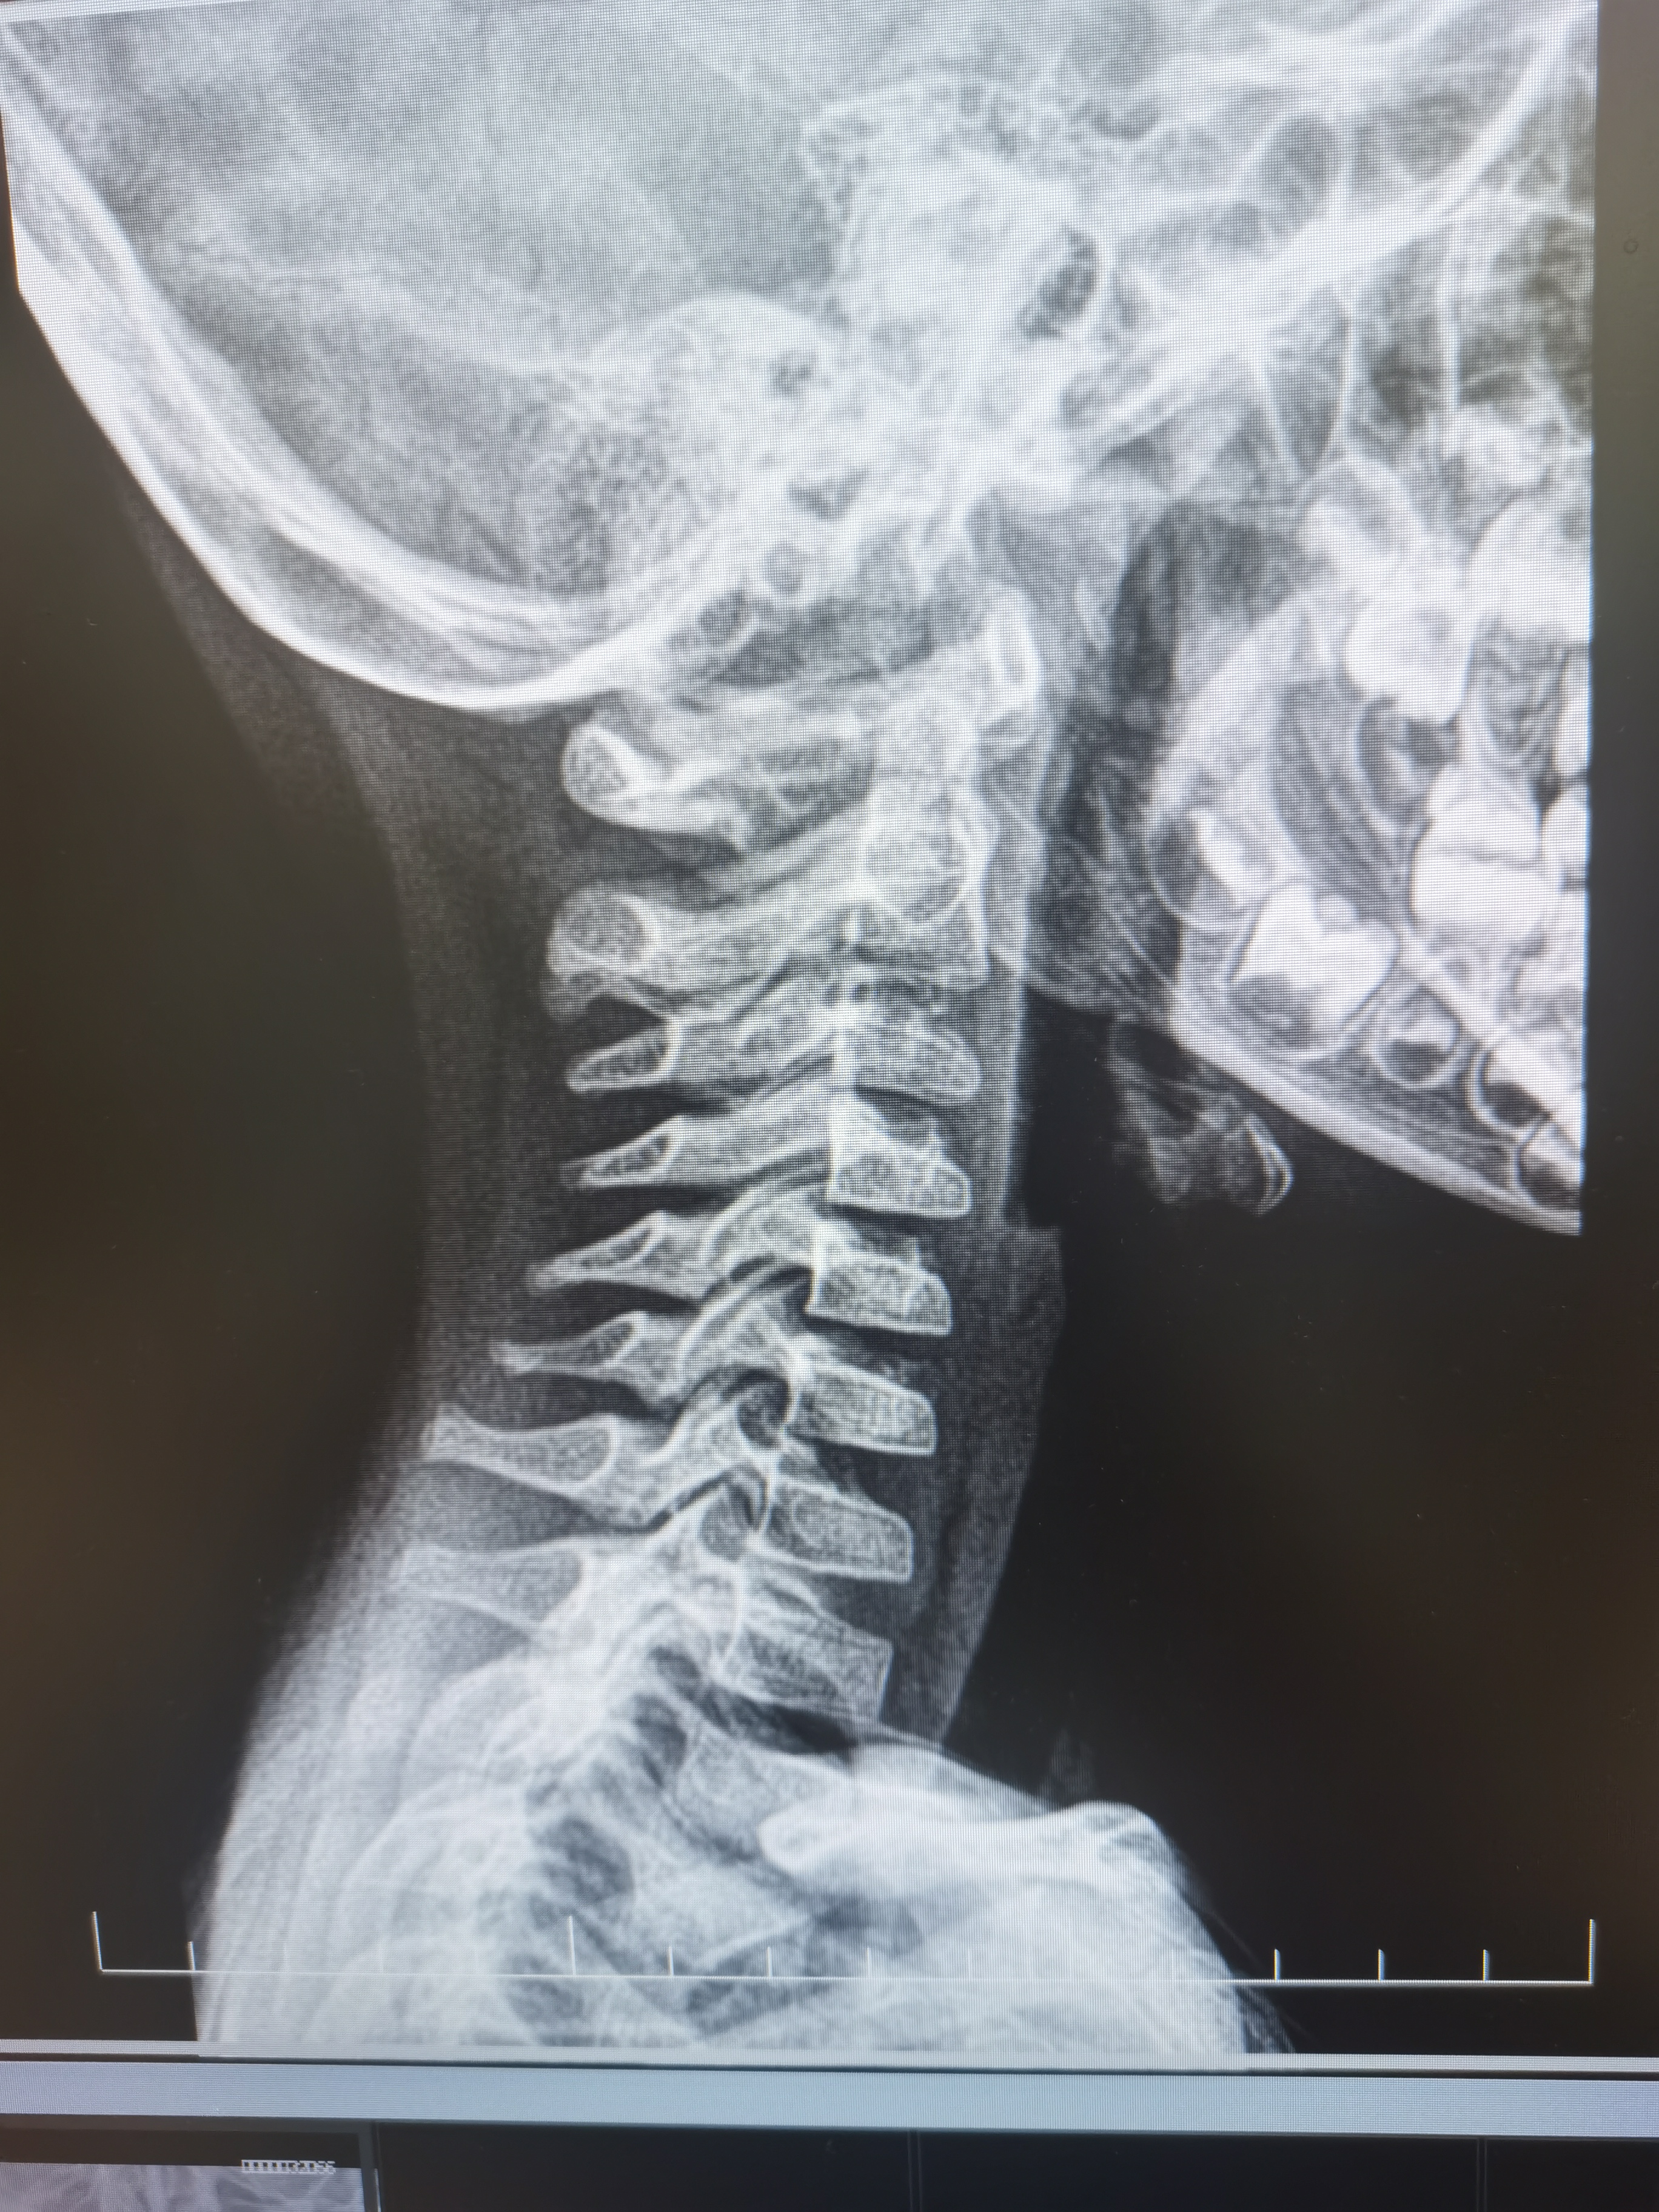

并且生理曲度都变直了,(见下图)

为什么会这样呢?这还只是一个四岁的小朋友呢!我们要知道小儿在2月时候开始出现抬头的动作,颈椎凸向前的生理曲度就开始出现了,如果我们总是低着头,颈椎的曲度就会慢慢变直,甚至出现反张,就会影响颈椎旁边的肌肉,容易造成紧张疼痛,继续发展的话旁边神经、血管、脊髓受压或者刺激还会出现一系列的症状产生颈椎病。询问患者家长得知,患儿喜欢趴着睡觉,并且还头向左侧旋转趴睡更多,因为缺少大人的陪伴,平时在家里喜欢一个人坐在地上低头玩玩具。那么诊断就非常清楚了,长期的头部左侧旋转趴睡造成了颈椎整体的旋转错位,长期的低头玩玩具造成了颈椎生理曲度的变直。还是我既往说的那句话,运动也是要讲究阴阳平衡的。